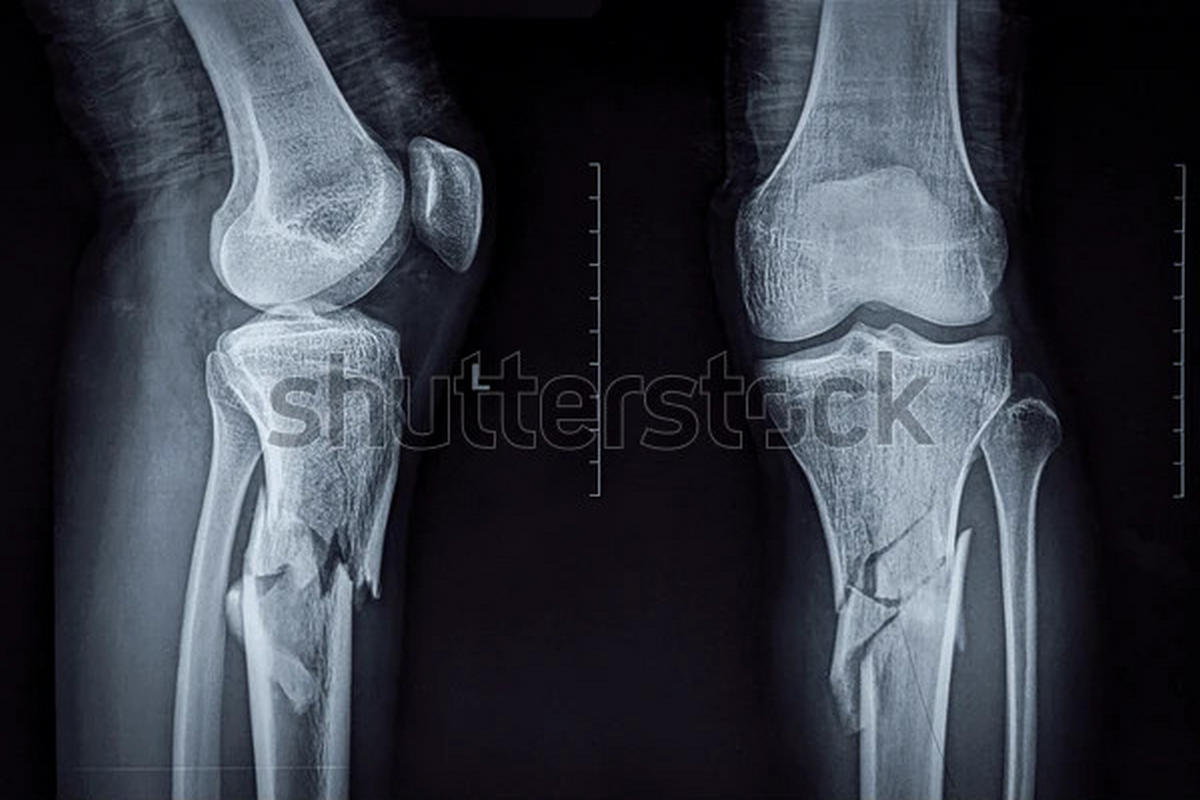

Κατάγματα κνημιαίων κονδύλων

Τα κατάγματα κνημιαίων κονδύλων αφορούν την άνω επιφάνεια της κνήμης, η οποία συμμετέχει άμεσα στη διαμόρφωση της άρθρωσης του γόνατος.

Εμφανίζονται συχνά μετά από τροχαία ατυχήματα, αθλητικούς τραυματισμούς ή πτώσεις. Τα συμπτώματα περιλαμβάνουν πόνο, οίδημα, δυσκολία στην κίνηση και συχνά αιμάρθρο.

Ιδιαίτερη σημασία έχουν οι συνοδές βλάβες σε μηνίσκους και συνδέσμους, οι οποίες επηρεάζουν την πρόγνωση. Εκτός από τις ακτινογραφίες, σχεδόν πάντα απαιτείται αξονική τομογραφία για λεπτομερή χαρτογράφηση του κατάγματος.

Μη παρεκτοπισμένα κατάγματα μπορούν να αντιμετωπιστούν συντηρητικά με ακινητοποίηση, αποφόρτιση και σταδιακή κινητοποίηση. Παρεκτοπισμένα ή ενδοαρθρικά κατάγματα απαιτούν χειρουργική ανάταξη και σταθεροποίηση με πλάκες ή βίδες. Η φυσικοθεραπεία είναι απαραίτητη για την πρόληψη δυσκαμψίας και δευτερογενούς αρθρίτιδας.